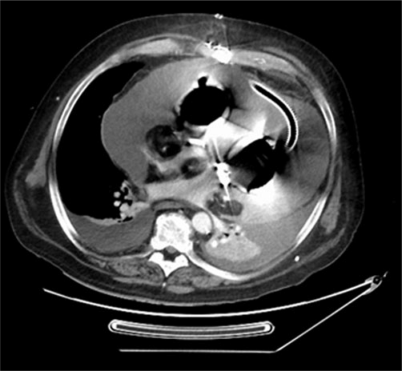

Die Ausflusstraktprothesen mit ihren Konnektoren werden in End-zu-End-Technik mit der aszendierenden Aorta und dem Truncus pulmonalis anastomosiert. Auf eine absolute Hämostase muss bei allen Anastomosen geachtet werden, da sie nach Einbringen der Pumpkammern nicht mehr einsehbar sind und potenzielle Blutungen nachträglich nur mit extremem Aufwand saniert werden können (Abb. 1).

Abb. 1

Intraoperativer Situs nach Resektion beider Ventrikel. Atriale Manschetten sind aufgenäht, ebenso Ausflusstraktprothesen an die Aorta ascendens bzw. den Truncus pulmonalis. Über diese Cuffs werden die künstlichen Ventrikel mit den Vorhöfen bzw. mit Aorta und Truncus pulmonalis konnektiert. 1 Rechte Vorhofmanschette; 2 linke Vorhofmanschette; 3 Prothese Aorta ascendens; 4 Prothese Truncus pulmonalis